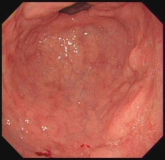

内镜下表现:黏膜红白相间,以白色为主,黏膜皱襞变平或消失,部分黏膜血管显露,可伴有黏膜颗粒或结节状等表现。如伴有肠化生于电子染色窄带成像放大内镜(NBI ME)下发现胃粘膜上皮细胞表面的脑回样结构嵴部的纤细浅蓝色线样结构。病理活检可进一步确诊。

萎缩胃表现